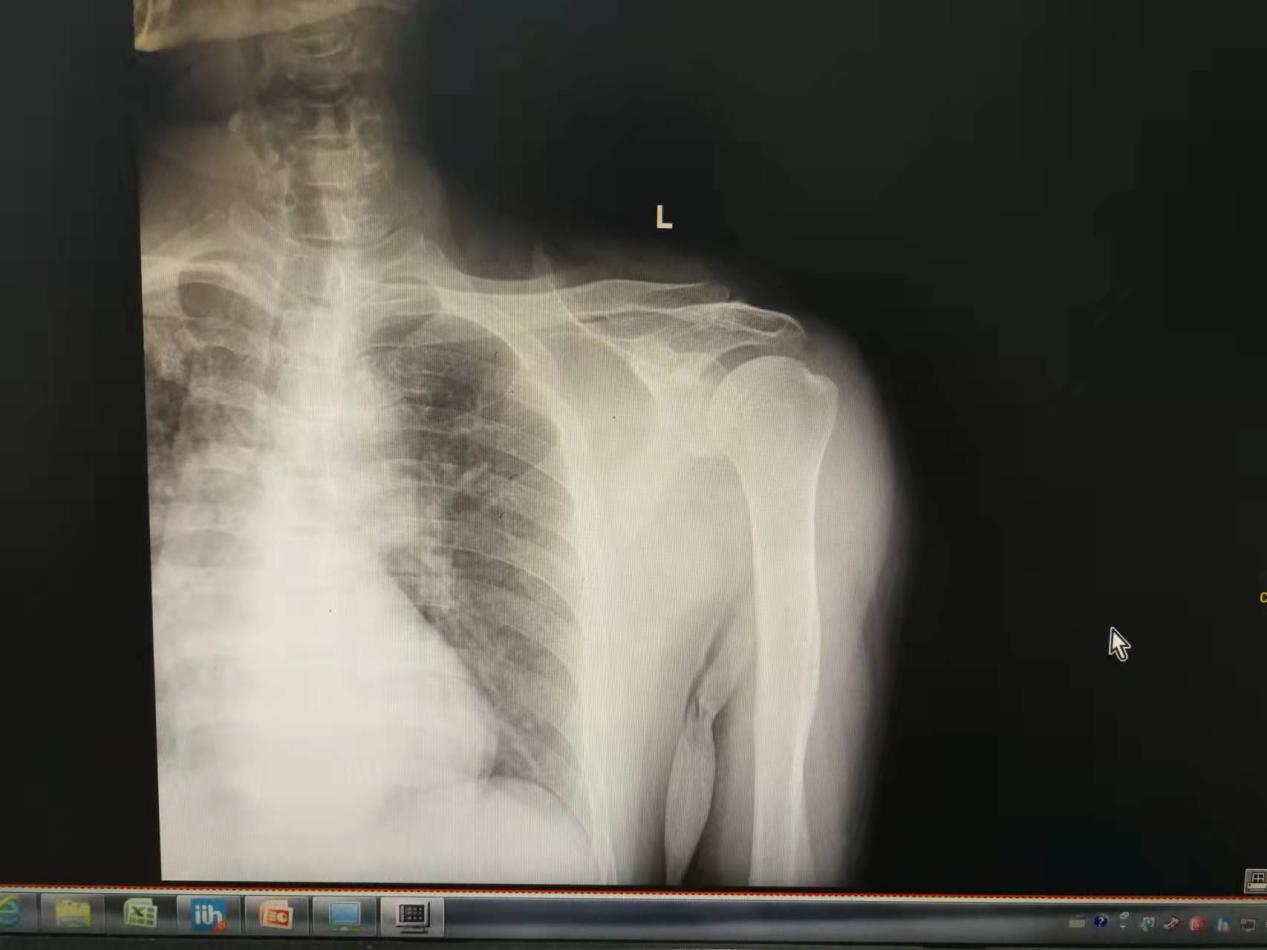

经过医生的手法复位,患者活动明显好转,疼痛明显减轻。

患者仰卧位,沿肱骨轴线方向牵引,如肱骨头与关节盂后缘有交锁,则需轻柔内旋上臂,同时给予侧方牵引力以松脱肱骨头与盂缘的嵌插绞锁,此时从后方推肱骨头向前,同时外旋肱骨即可复位。复位成功的关键是肌肉应完全松弛,因此应在充分的麻醉下进行手法复位,力求轻柔,避免强力外旋,以免造成肱骨头或颈部骨折。复位后如较为稳定,可用吊带或包扎固定于胸侧,将上臂固定于外展30°,后伸30°,旋转,前臂中立位四周,如复位后肱骨头不稳定,则需将上臂置于外旋轻度后伸位以肩人字石膏或支具固定,也可在复位后以克氏针通过肩峰交叉固定肱骨头。三周后去除固定,开始练习肩关节活动。手法复位不成功的话,就需要进行手术复位!